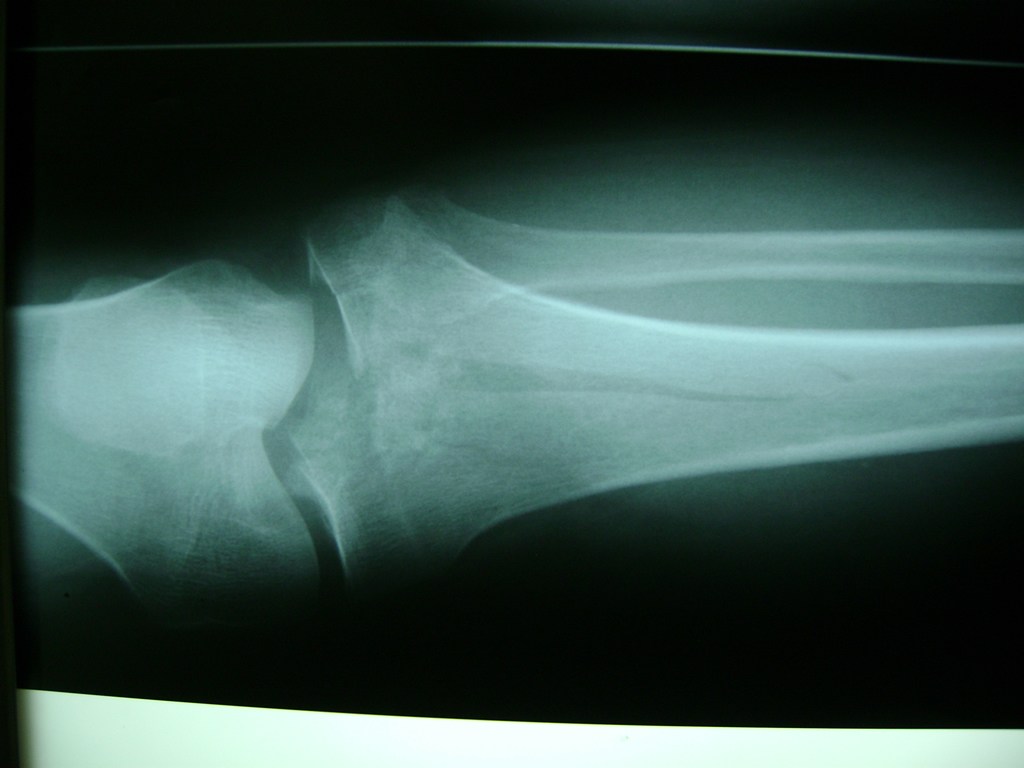

Cirugías de Codo - Rodilla

La artroscopia de rodilla es un cirugía en el cual la estructura interna de la articulación es examinada ya sea para realizar un diagnostico o para realizar un tratamiento, este procedimiento se realiza utilizando un instrumento parecido a un pequeño tubo llamado artroscopio.